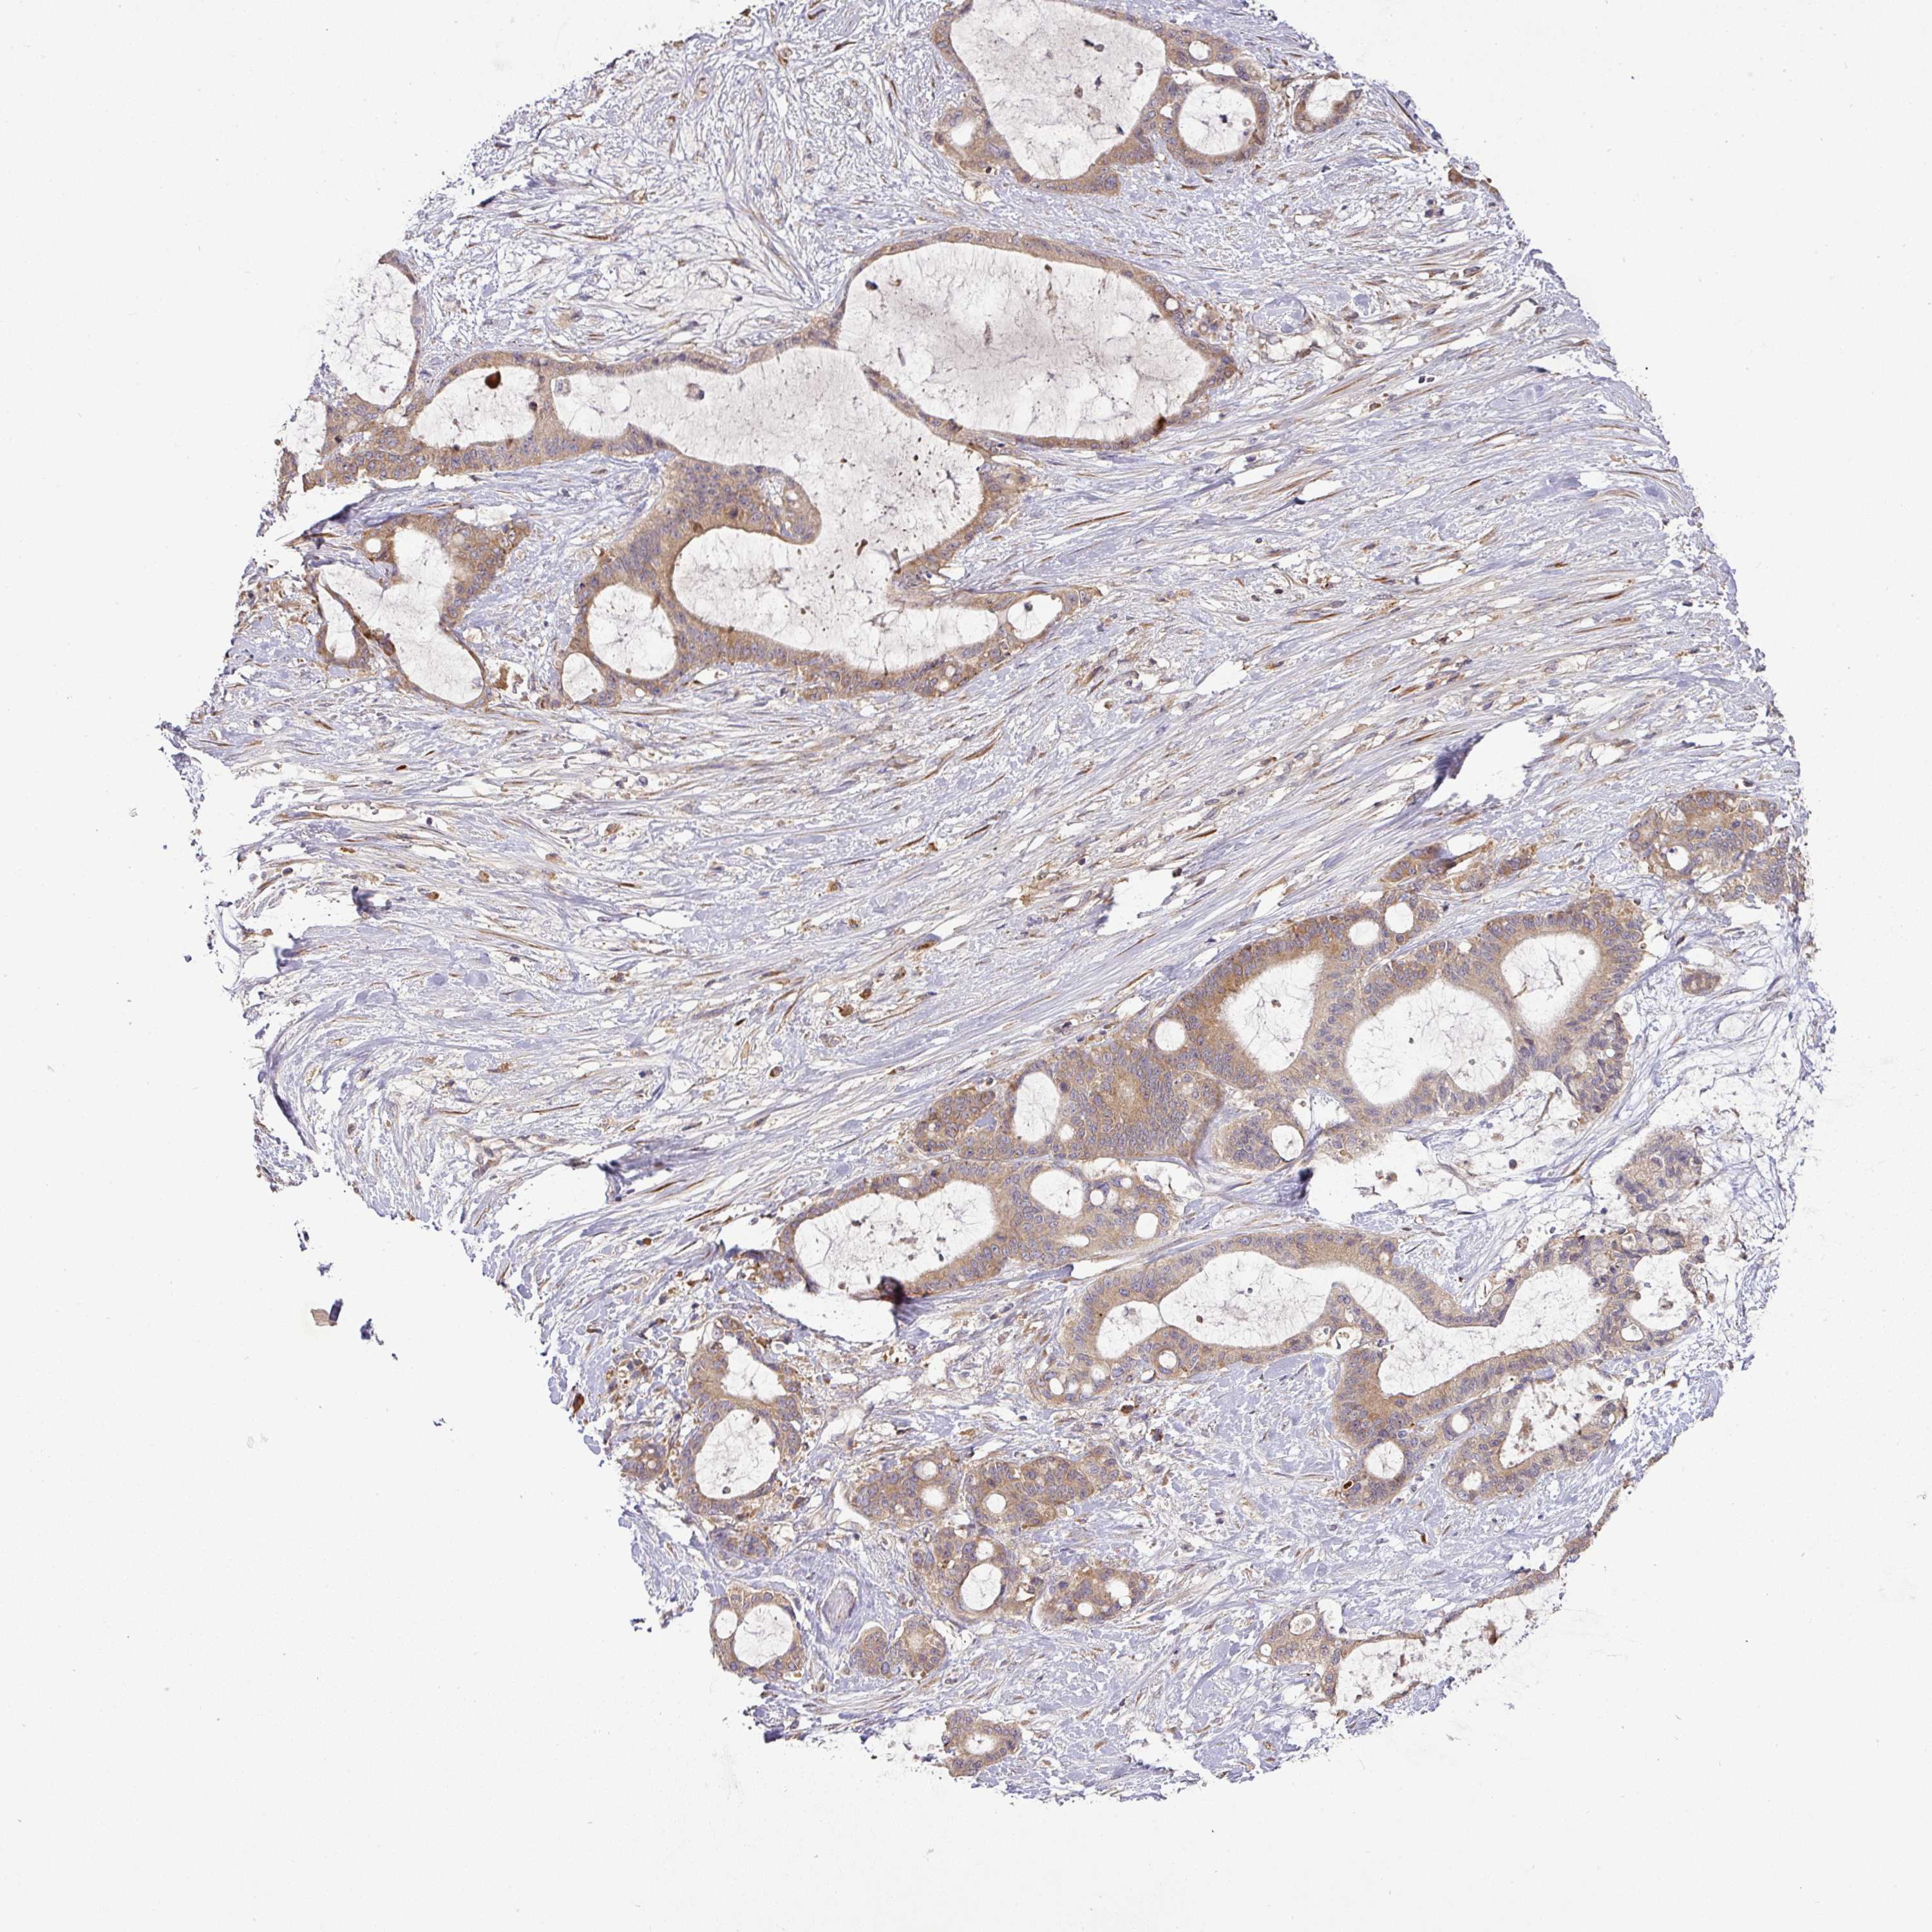

LIVER CANCER - Protein expressioni

A mouse-over function shows sample information and annotation data. Click on an image to view it in a full screen mode. Samples can be filtered based on level of antibody staining by selecting one or several of the following categories: high, medium, low and not detected. The assay and annotation is described here.

Note that samples used for immunohistochemistry by the Human Protein Atlas do not correspond to samples in the TCGA dataset.

Antibody stainingi

Antibody staining in the annotated cell types in the current human tissue is reported as not detected, low, medium, or high, based on conventional immunohistochemistry profiling in selected tissues. This score is based on the combination of the staining intensity and fraction of stained cells.

Each image is clickable and will lead to virtual microscopy that enables deeper exploration of all samples and also displays staining intensity scores, fraction scores and subcellular localization as well as patient and tissue information for each sample.

Antibody HPA053938

Staining

High

Medium

Low

Not detected

Intensity

Strong

Moderate

Weak

Negative

Quantity

>75%

75%-25%

<25%

None

Location

Nuclear

Cytoplasmic/membranous

Cytoplasmic/membranous,nuclear

Carcinoma, Hepatocellular, NOS

Cholangiocarcinoma